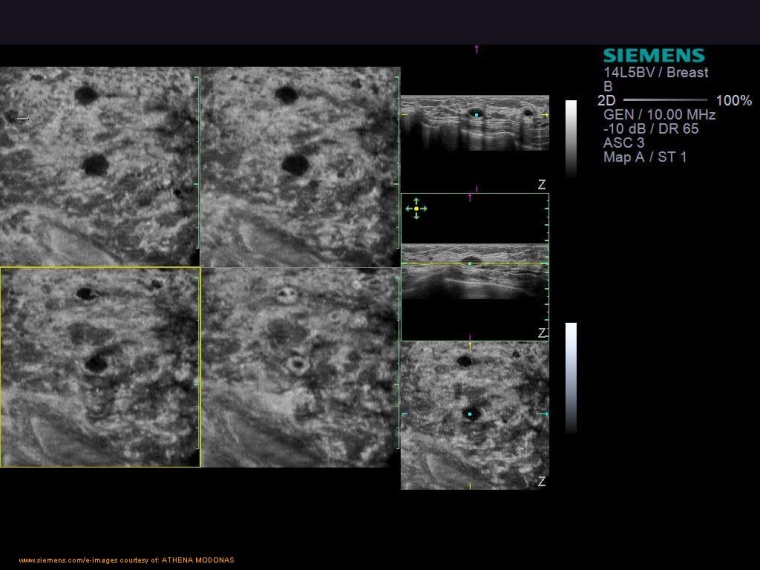

Ultraschall zur Brustkrebsdiagnose

Gegenwärtig wird in den meisten westlichen Ländern zur Früherkennung die Screening-Mammographie als Methode der Wahl angesehen, da sie der weltweit am weitesten verbreitete Kompromiss zwischen Vor- und Nachteilen sowie Kosten darstellt. Warum Leitlinien bei erhöhter Brustdichte die ergänzende Sonographie empfehlen lesen Sie in unserem Whitepaper zum Download.